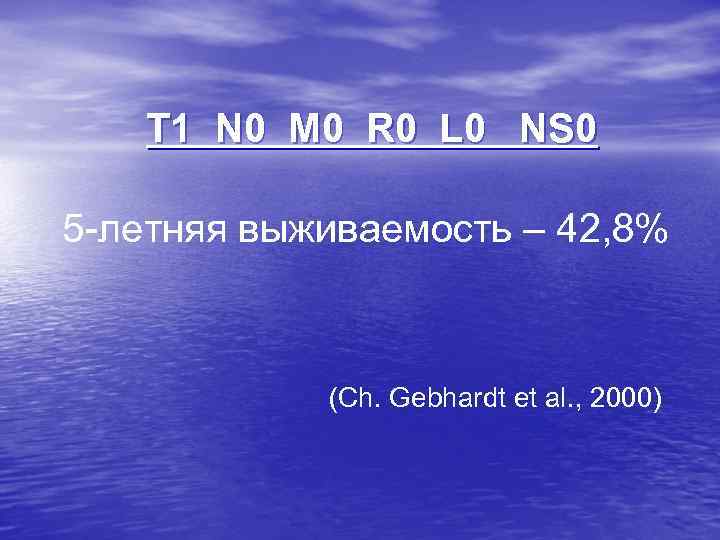

T 1 N 0 M 0 R 0 L 0 NS 0 5 -летняя выживаемость – 42, 8% (Ch. Gebhardt et al. , 2000)